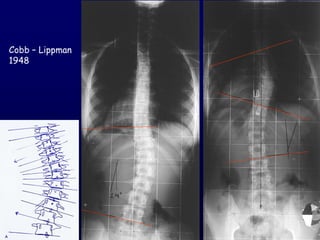

Cobb – Lippman

1948

Out of balance (cm)

Οζηηθή ειηθία

Αηιαξ Greulich & Pyle

Θαγόκηα επίθοζε

Risser 1958

΢θειεηηθή ςνίμακζε

Risser 1 Risk for progression 60-70%

3 10%

Peterson LE, Nachemson AL 1995

Side bending view